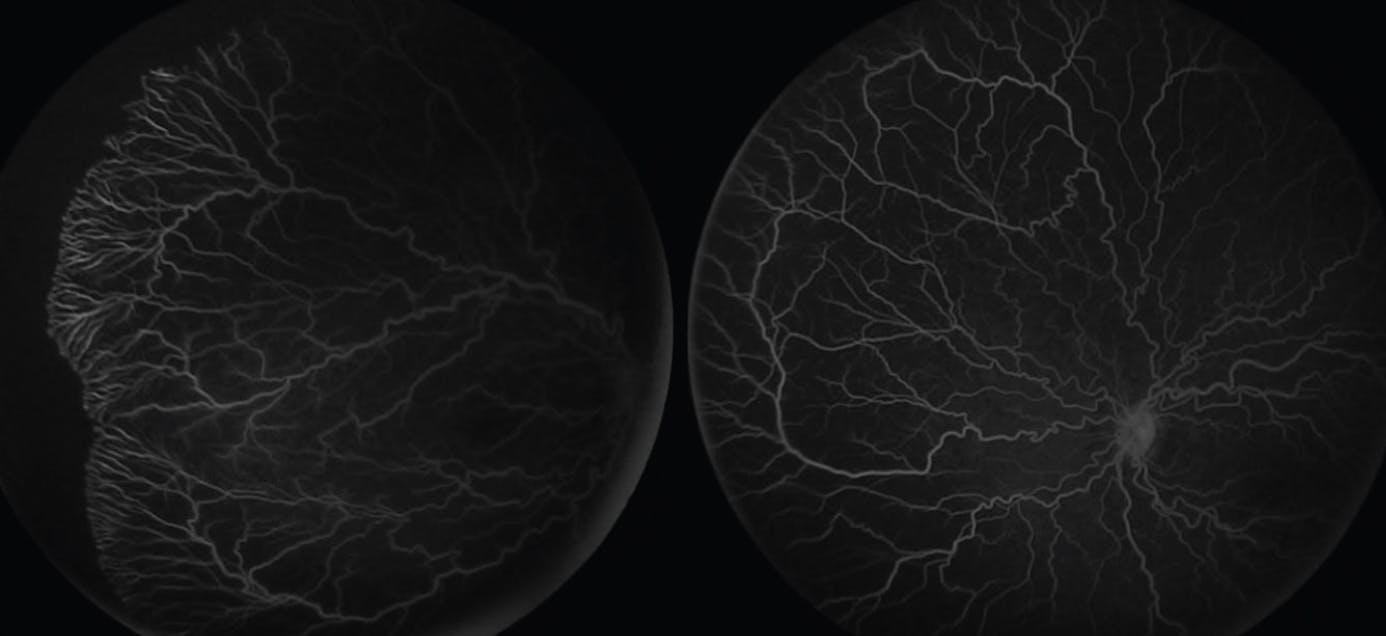

FA is most commonly obtained using contact-based imaging modalities and is performed in the OR as part of an examination under anesthesia (Figures 1 and 2). With the increased use of anti-VEGF injections in ROP, FA can help to provide valuable information on the presence and degree of peripheral avascular retina and can guide laser treatment. It may also improve the sensitivity of diagnosis of stage 2 or worse disease.4,5

Figure 1. FA imaging shows a peripheral avascular retina and persistent vessel tortuosity following regression of disease in a neonate with severe cardiopulmonary disease.

<p>Figure 2. This side-by-side comparison shows the utility of FA alongside fundus photography in the case of type 1 ROP treated previously with bevacizumab that later developed flat neovascularization within a fibrotic ridge.</p>

Figure 2. This side-by-side comparison shows the utility of FA alongside fundus photography in the case of type 1 ROP treated previously with bevacizumab that later developed flat neovascularization within a fibrotic ridge.